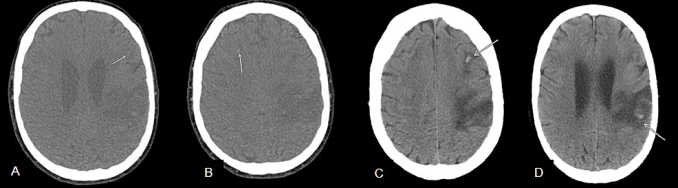

Am dritten Tag ihres Aufenthalts verschlimmert sich der Sauerstoffmangel der Frau so sehr, dass sie intubiert und künstlich beatmet wird. Weitere Blutgerinnsel in der Lunge werden festgestellt. An Tag sieben ihrer Leidenszeit im Krankenhaus beginnen die Nieren Zeichen eines bevorstehenden Versagens von sich zu geben. Eine Autoimmunerkrankung wird festgestellt und ein Blutplasma-Austausch begonnen. Sie wird in eine Spezialklinik verlegt. In den ersten Tagen ihres dortigen Verbleibs verschlechtert sich ihr neurologischer Zustand. Eine Computertomographie zeigt Blutgerinnsel in beiden Schläfenlappen, sowie sie umgebenden Flüssigkeitseinlagerungen.

(Figure 3 A-D).